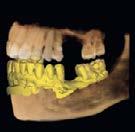

Segunda fase quirúrgica de impactación maxilar Lefort I, 4 mm, (Figura 7), se realizó la cirugía mandibular que consistió en la osteotomía sagital de la rama bilateral de avance, 9 mm (Figura 8), se hizo la cirugía del mentón con la mentoplastía de avance 4 mm, (Figura 9) y una fase postquirúrgica de detallado y retención.

Fueron realizados después de 1 año y 2 meses de haber iniciado el tratamiento y después de la cirugía. En los estudios radiológicos tenemos que en la radiografía lateral de cráneo las placas utilizadas para consolidar la fijación de los maxilares, la corrección de las relaciones esqueléticas en la Figura 10. En la panorámica inicial se señalan los gérmenes de los terceros molares (Figura 11) y en la Figura 12, la realización de las exodoncias de órganos dentarios 18, 28, 38 y 48.

En la sobreimposición del componente craneofacial inicio (color negro) y final (color rojo), se observa un paciente con crecimiento, con cambio a nivel de los labios superior e inferior. Con rotación mandibular hacia adelante y hacia arriba, debido a la Lefort I con impactación de 4 mm. El avance mandibular de 9 mm y la mentoplastía de avance de 4 mm (Figura 17).